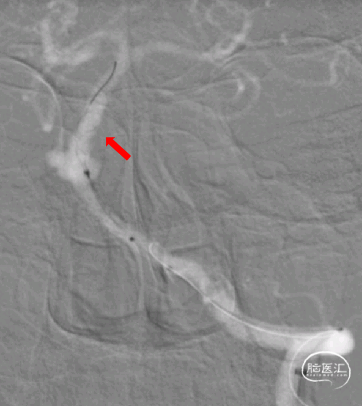

主动脉弓造影

正侧位造影

3D旋转造影

通过3D工作位测量出基底动脉瘤瘤颈最宽处:6.5mm;载瘤动脉尺寸:近端直径3.7mm,远端直径4.2mm。